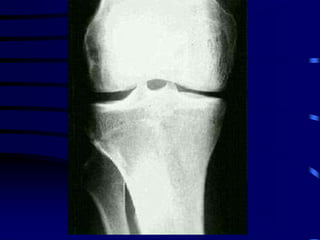

OSTEOARTRITIS

CORRELACION ANATOMO-RADIOLOGICA

PATOLOGIA RADIOLOGIA

Fibrilación y erosión cartilaginosa Pinzamiento articular

Prolifer. celular en hueso subcondral Esclerosis ósea

Intrusión de LS o contusión ósea Quistes subcondrales

Proliferación marginal Osteófitos

Distorsión capsular y ligamentaria Deformidad y desalineación

Osteoartritis: Características Generales

•Osteófitos

•Pinzamiento

articular

•Quistes

subcondrales y

esclerosis

•Desalineación